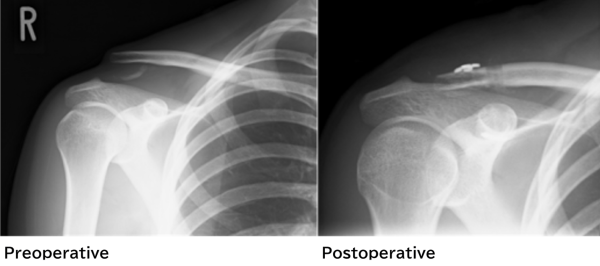

Illustration 1 shows the dislocation of acromioclavicular. Chronic acromioclavicular dislocation is a dislocation which happened a while ago, therefore, the procedure for an acute dislocation (Illustration 2) is not applicable. So, what should we do?

Illustration 3 shows the procedure for chronic acromioclavicular dislocation.

The procedure starts with making tunnels on the acromioclavicular and the coracoid process to put the autologous semitendinosus tendons to tie the two joints. The thread made with tendons stays screwed until it adheres to the joints. After that, these two joints are clamped with the thread and two end-buttons as in the treatment for acute dislocation. Finally, the edge of autologous semitendinosus tendons is fixed onto the acromion (Illustration 4).